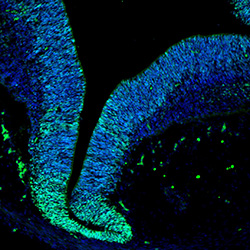

An anatomical analysis of the developing human midbrain from 6 post-conceptional weeks (PCW) to 22 PCW reveals increased tissue complexity, characterized by the emergence of dopaminergic nuclei, as highlighted by immunofluorescence analysis for tyrosine hydroxylase (TH).

6PCW

DAPI

6PCW human midbrain

KI67

Merged